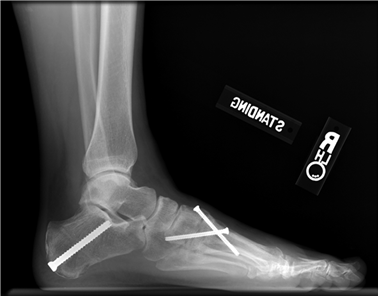

Weight-bearing anteroposterior (AP), lateral, and sesamoid axial radiographs are mandatory. On the AP view, the surgeon measures the Hallux Valgus Angle (HVA, normal < 15°), the Intermetatarsal Angle (IMA, normal < 9°), and the Distal Metatarsal Articular Angle (DMAA). The lateral view is scrutinized for Meary's angle (talo-first metatarsal angle) to identify midfoot collapse, as well as the presence of dorsal osteophytes indicative of hallux rigidus. The sesamoid axial view is critical for assessing the degree of sesamoid subluxation and the integrity of the crista.

To achieve multiplanar correction, the surgeon must address the sagittal, coronal, and transverse planes. The first metatarsal is plantarflexed to restore the longitudinal arch, rotated out of pronation to realign the sesamoids, and translated laterally to close the IMA. Subchondral drilling or feathering is performed to optimize the biological environment for fusion. Fixation is traditionally achieved with two or three crossed solid or cannulated screws (typically 3.5mm or 4.0mm). Recently, plantar or medial locking plates have gained immense popularity due to their superior biomechanical construct, allowing for earlier weight-bearing. Bone graft or orthobiologics may be packed into the arthrodesis site to stimulate osteogenesis.